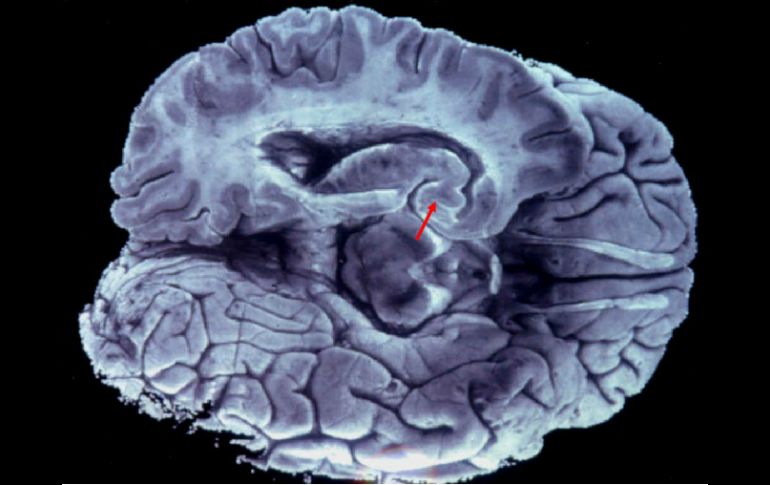

Se comprobó que cuanto más activa era la proteína es menor la esperanza de vida de los pacientes. EFE / ARCHIVO

Se trata del primer trabajo que muestra cómo el gen que codifica la proteína llamada OSMR es un componente fundamental para la proliferación del glioblastoma, un tumor cerebral difícil de operar y que puede mostrar resistencia a la radioterapia y la quimioterapia.